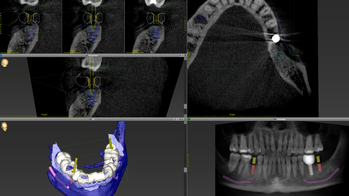

Operationsplanung

Die Planung des Eingriffs erfolgt an unserer Klinik durch eine dreidimensionale Simulation der Bewegungen der zahntragenden Anteile der Kiefer anhand einer zuvor angefertigten DVT (digitale Volumentomografie, modernes 3D-Röntgenverfahren). Die für die Durchführung der Operation erforderlichen Schienen (Splints) können so ebenfalls in optimaler Passung 3D-gedruckt werden.

Alternativ kann die Operation „klassisch“ über Gipsmodelle in einem sogenannten Artikulator geplant werden. Die optimale Kiefer- und Zahnposition wird in der Regel über ein simultanes Verschieben des Ober- und Unterkiefers erreicht (bignathe Umstellungsoperation). In Einzelfällen und bei geringen Fehlstellungen kann ein operatives Verlagern von nur einem Kiefer ausreichend sein, auch als monognathe Umstellungsoperation bezeichnet. Die Dauer des stationären Aufenthaltes sowie die Nachbehandlung sind bei beiden Operationsformen identisch.

In direkter Nachbarschaft des Kiefers verlaufen wichtige Strukturen wie etwa Nerven und Gefäße. Um das Risiko einer Verletzung und die Ausdehnung der Operation so gering wie möglich zu halten, empfehlen wir in bestimmten Fällen vor dem Eingriff eine 3D-Röntgendiagnostik, bekannt als Digitale Volumentomographie (DVT). Diese Art der Bildgebung wird jedoch von den gesetzlichen Krankenkassen in der Regel nicht übernommen.

Ein weiterer Fokus unserer Klinik für Mund-, Kiefer- und Gesichtschirurgie am UKS liegt auf der dentalen Implantologie für komplexe Fälle und vorerkrankte Patientinnen und Patienten. Zahnimplantate werden zur Verankerung von Kronen, Brücken oder Prothesen im Kiefer eingesetzt und zielen auf die Wiederherstellung der Kaufähigkeit ab. Eine präzise Planung der Operation ist entscheidend, um Implantate optimal zu positionieren und angrenzende Risikostrukturen zu schützen. Dabei nutzen wir häufig digitale Planungsprogramme, die durch spezielle Schablonen die Präzision und Sicherheit während der Operation verbessern. Zahnimplantate sind in der Regel keine Leistung der gesetzlichen Krankenkassen, außer bei Patienten mit Tumorerkrankungen oder angeborenen Fehlbildungen. Wir beraten Sie gerne zu individuellen Lösungen für Ihre dentale Rehabilitation, auch in Kooperation mit Ihrer Hauszahnärztin oder Ihrem Hauszahnarzt.